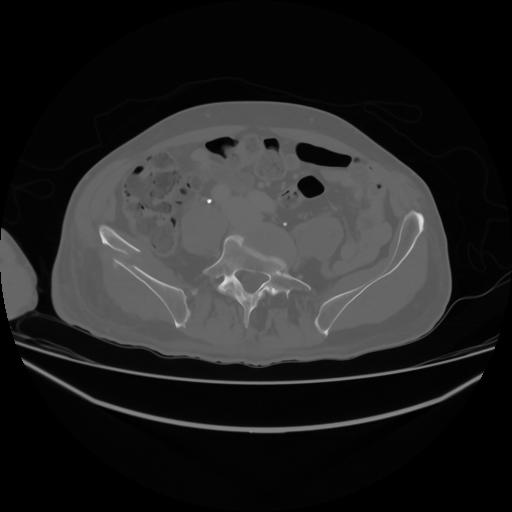

4 CUERPO,CE,Axial,3.0,CUERPO,,